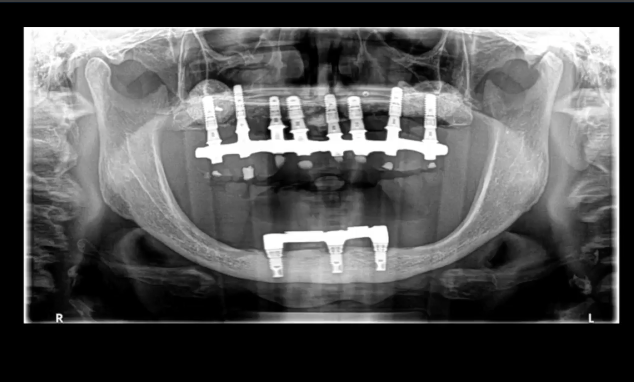

Pterygoid implants are an old therapeutic option for the

treatment of atrophic posterior maxilla that is often overlooked in today’s

treatment options. This lecture addresses the perceived anatomical risk that is

often associated with this procedure and tries to elucidate the controversies

on the subject. It will expose the scientific documentation of the procedure

and will present the modern approach in using the pterygoid implant for the

rehabilitation of totally and partially edentulous patients. The place of

guided surgery in performing this procedure is also discussed.